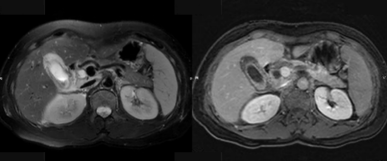

腺炎MRI表现:胰腺局限/弥漫肿大,呈T1低信号、T2高信号;胰腺轮廓清楚或模糊,渗出明显者可有胰周 或胰外积液,呈T1低信号、T2高信号;合并出血,T1T2皆呈高信号;增强扫描:水肿型,胰腺均匀强化 ;坏死型,胰腺不均匀强化,坏死区无明显强化。

截屏2022-10-06 18.55.47